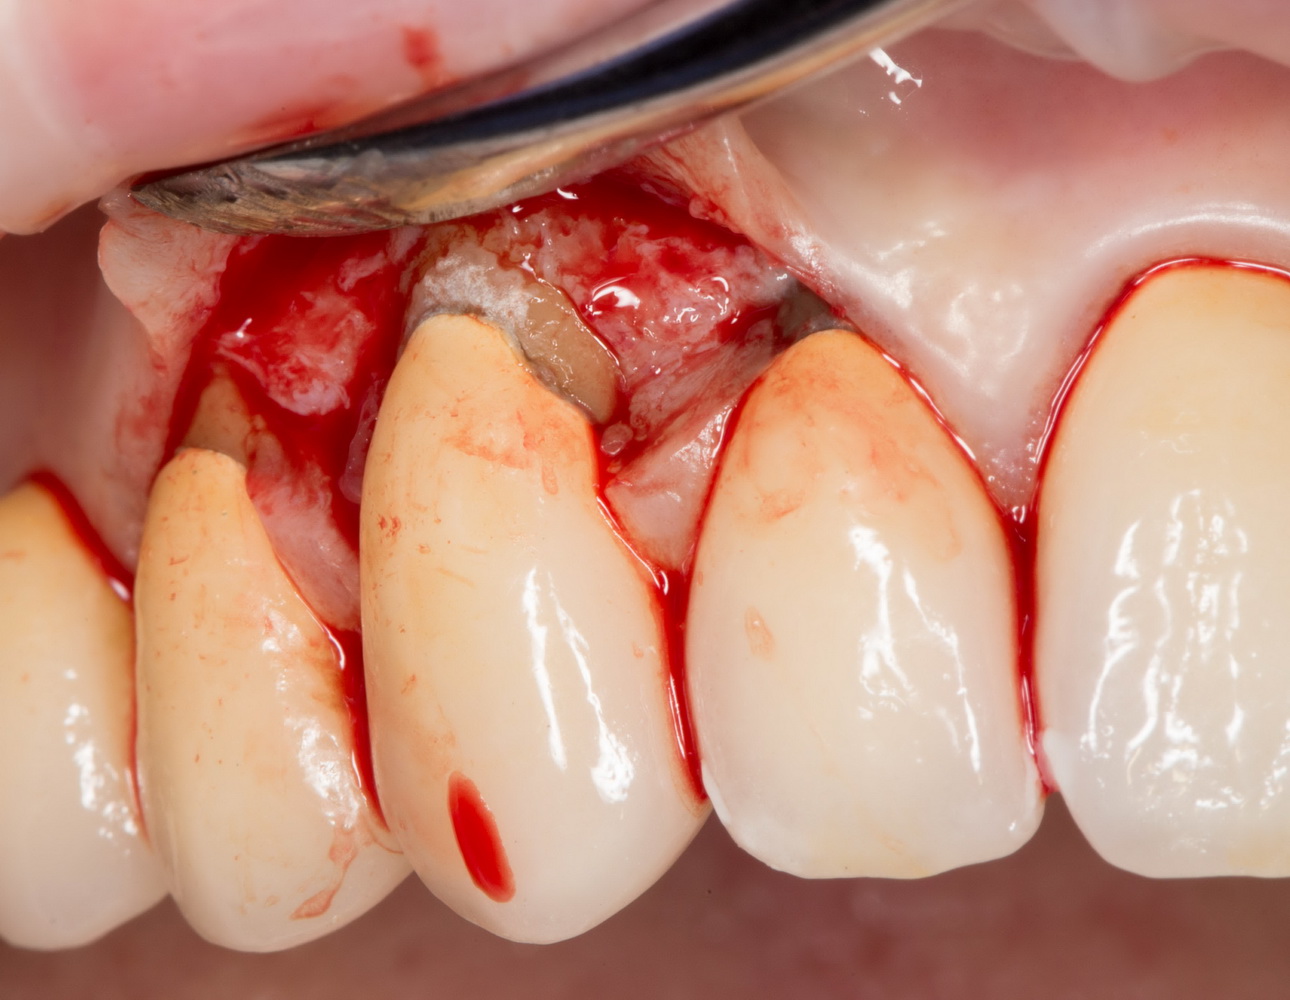

Самым доступным является остеопластика методом аутотрансплантации костных блоков:

![]() остеопластика методом аутотрансплантации костных фрагментов, проведенная одновременно с имплантацией. Такими методами можно легко и безопасно восстановить небольшие объемы утраченной костной ткани, существенно сократить срок и стоимость имплантологического лечения |

![]() через 3 месяца после операции — недостающая костная ткань полностью восстановлена, имплантат интегрирован |

однако, этот метод связан с одним неприятным моментом, а именно — необходимостью донорского участка, из которого производится забор аутокостного фрагмента. Другими словами, это относительно травматичная методика. Но она не требует использования биоматериалов и, при правильной адаптации аутотрансплантата — барьерной мембраны, отличается высокой надежностью, предсказуемостью и низкой себестоимостью.

Другой метод остеопластики называется «направленной тканевой (или костной) регенерацией». Для успешной его реализации необходимы барьерные мембраны, нередко — дополнительные биоматериалы, пины и т. д., что существенно (иногда в два раза) повышает стоимость хирургического вмешательства. Но живые клетки — основа регенерации костной ткани, — в этом случае забираются в виде аутокостной стружки, а не блока, поэтому травматичность данного метода ниже, чем при аутотрансплантации. Результаты, предсказуемость, надежность — те же самые: